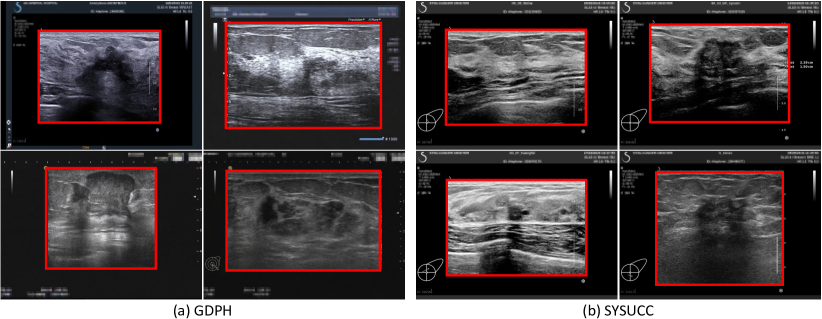

Refer to caption

Figure 4: Some examples of breast ultrasound images in two medical centers, (a) GDPH and (b) SYSUCC. The red boxes are the foreground images we extract.

IV-C GDPH&SYSUCC

In this study, we also construct a publicly available dataset of BUS images for breast cancer diagnosis. The BUS images came from two medical centers. 1) the Department of Ultrasound, Guangdong Provincial People’s Hospital, Guangzhou, Guangdong, China (GDPH). 2) the Department of Ultrasound, Sun Yat-sen University Cancer Center, Guangzhou, Guangdong, China (SYSUCC). We exported the images and their corresponding BI-RADS scores from the picture archiving and communication system (PACS). The ultrasound images were acquired from following equipments, including Hitachi Ascendus (Japan), Mindray DC-80 (China), Toshiba Aplio 500 (Japan) and Supersonic Aixplorer (France). All the images were labeled as benign or malignant according to the pathology report after the biopsy or surgery was performed. The dataset consists of 1519 malignant BUS images from 676 patients and 886 benign BUS images from 526 patients, for a total of 2405 BUS images. The average size of the images is 844×627844627844\times 627 and the range from 278×215278215278\times 215 to 1280×80012808001280\times 800. Fig. 4 shows some examples of BUS images in our dataset. To protect the privacy of the patients, we mosaic the personal information. The distribution of the BI-RADS scores and the statistics of the malignant tumors and the benign tumors are shown in Table I.

IV-C1 Data Preprocessing

All the images are exported from the picture archiving and communication system (PACS). We extract the image data from the original DICOM format files of BUS and save them in PNG format. To exclude the UI regions, we extract the foreground images by applying a rectangle detection algorithm provided by the OpenCV library, and manually check all the images to ensure the completeness of the foreground images.